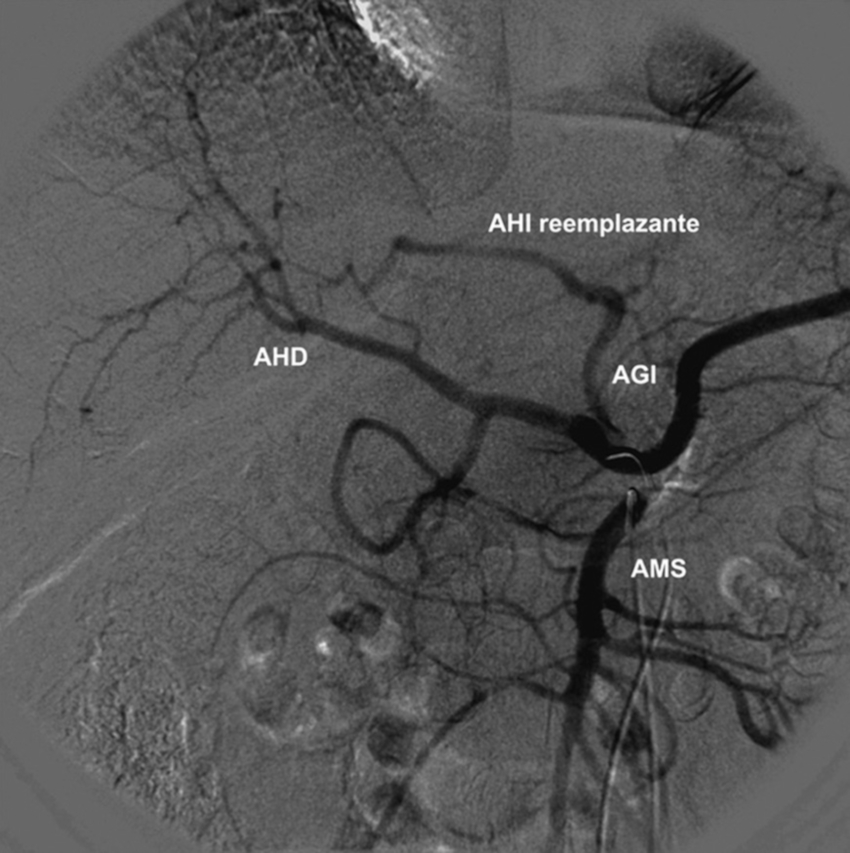

Tipo 3: AHD aberrante con origen en la AMS. AHI con origen en la AHC (Figs. 6 y 7).

La población estudiada fue de 275 pacientes, con una edad mediana de 58.5 años y de sexo masculino el 73.1% (n = 201). Se han constatado las variantes tipo 1 (normal) de anatomía de la arteria hepática en 192 casos (69.8%), tipo 2 en 18 casos (6.5%), tipo 3 en 19 casos (6.9%), tipo 4 en 7 casos (2.5%), tipo 5 en 4 casos (1.5%), tipo 6 en 3 casos (1.1%), tipo 7 en 2 casos (0.7%), tipo 8 en 7 casos (2.5%), tipo 9 en 17 casos (6.2%).

La variante anatómica más frecuente de vascularización hepática en esta investigación fue el tipo 1, que hemos encontrado en un 69.8% de nuestra serie. Esta frecuencia es superior a la descrita por Michels5) (55.0%) y Covey et al. (16) (61.3%); no obstante, es inferior a la reportada en la serie de Song et al. (17) (89.1%) y la revisión de Noussios et al. (15) (81.0%) (Tabla 1).

Las siguientes variantes más frecuentes halladas fueron los tipos 2, 3 y 9. Las prevalencias de los tipos 2 y 3 fueron cercanas a la reportada por Fonseca-Neto et al. (18; asimismo, destacamos la prevalencia aumentada de la variante de Michels tipo 9 en nuestra serie comparada con otras publicaciones5,13,15,17,19. Al igual que Covey et al. (16, no hemos detectado la variante de Michels tipo 10; sin embargo, observamos otros hallazgos infrecuentes fuera de la clasificación de Michels, como dos casos de tronco celíaco-mesentérico (0.7%), ausencia del tronco celíaco (emergencia independiente de la AHC y esplénica), AHI accesoria emergente de la AGD y la emergencia de las AHD e AHI aberrantes de la AMS. También hallamos tres casos con arco de Bühler (1.1%), con una frecuencia similar a la de otros reportes (1.0 a 4.0%)20.